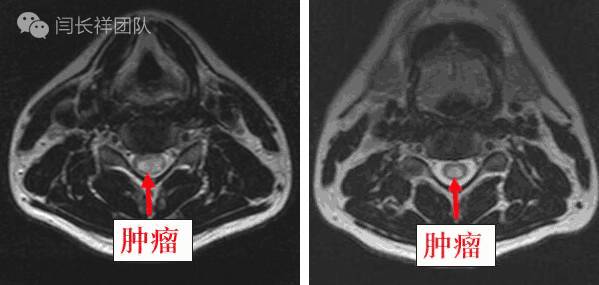

术前MRI示肿瘤位于髓内,显著压迫周围脊髓组织

颈5-胸1髓内占位,室管膜瘤